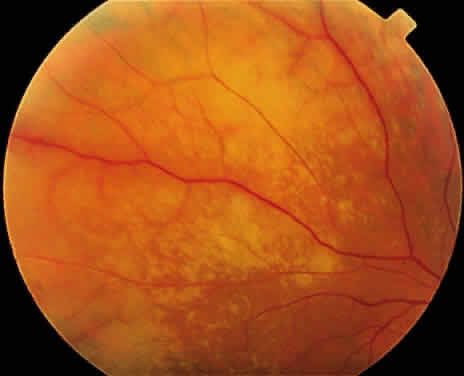

As the active retinal inflammatory process recedes, either spontaneously or with treatment, the retinal areas previously infected appear thinned and atrophic, with underlying retinal pigment epithelial alterations (Fig. 10). These pigmentary changes usually begin to develop around 4 weeks after the onset of the infection.22 Often a distinct scalloped pattern can be seen that clearly demarcates previously involved and spared retina (Fig. 11). The pigmentary alterations result from both retinal pigment epithelial cell death by direct infection and secondary inflammatory changes and hyperplasia induced by the adjacent retinal necrosis. Full-thickness retinal breaks are a prominent feature of the ARN syndrome, and often develop during the recovery stage of ARN. Retinal breaks may be large, irregular, and multiple and classically occur at the junction of normal and affected retina (Fig. 12)23; they can, however, occur elsewhere in the retina, with or without accompanying vitreous fibrosis and traction. Clarkson and coworkers noted traction-associated retinal tears in uninvolved retina.14 Rhegmatogenous retinal detachment is a major cause of visual loss and occurs in 50% to 75% of cases not treated with prophylactic laser photocoagulation.1,10,14 Retinal detachment caused by ARN usually develops several weeks after the onset of inflammation; however, retinal detachment has been reported as early as 6 days or as late as several months after the onset of symptoms.24 These detachments are often complicated because of the combined effect of vitreous organization and multifocal retinal breaks. Unusual late sequelae of ARN syndrome include neovascularization of the retina and optic disc with vitreous hemorrhage (Fig. 13).25,26 In contrast to other uveitic syndromes, chronic or relapsing episodes of intraocular inflammation are not common in ARN.27